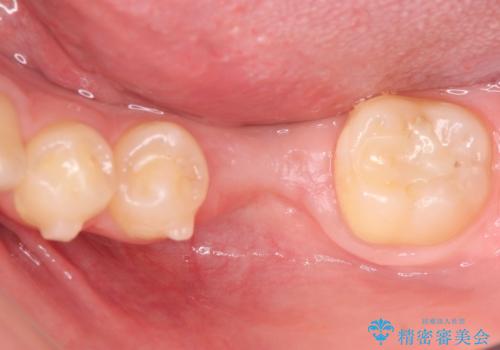

- 口の閉じにくさと割れてしまった奥歯を気にして来院された患者様です。

割れてしまった奥歯は抜歯し、矯正治療中の良いタイミングでインプラントを埋入することとしました。